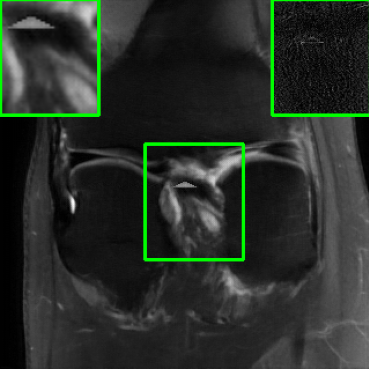

Figs. 4 and 5 show images reconstructed by different methods at 8x and 4x undersampling, respectively. The LONDN-MRI reconstructions (either iterative or oracle) show fewer artifacts, sharper features, and fewer errors than the global MoDL and initial aliased reconstructions. The iterative LONDN-MRI results are also quite close to the oracle result.

| Ground Truth | Global | LONDN-MRI | LONDN-MRI | Oracle |

| (1 iteration) | (2 iterations) | |||

![]() |

| PSNR = dB | PSNR = 32.78 dB | PSNR = 33.16 dB | PSNR = 33.25 dB | PSNR = 33.30 dB |

| Initial | DIP | SOUP-DIL | RAKI | LORAKI |

| PSNR = 21.23 dB | PSNR = 30.18 dB | PSNR = 30.66 dB | PSNR = 31.26 dB | PSNR = 31.67 dB |